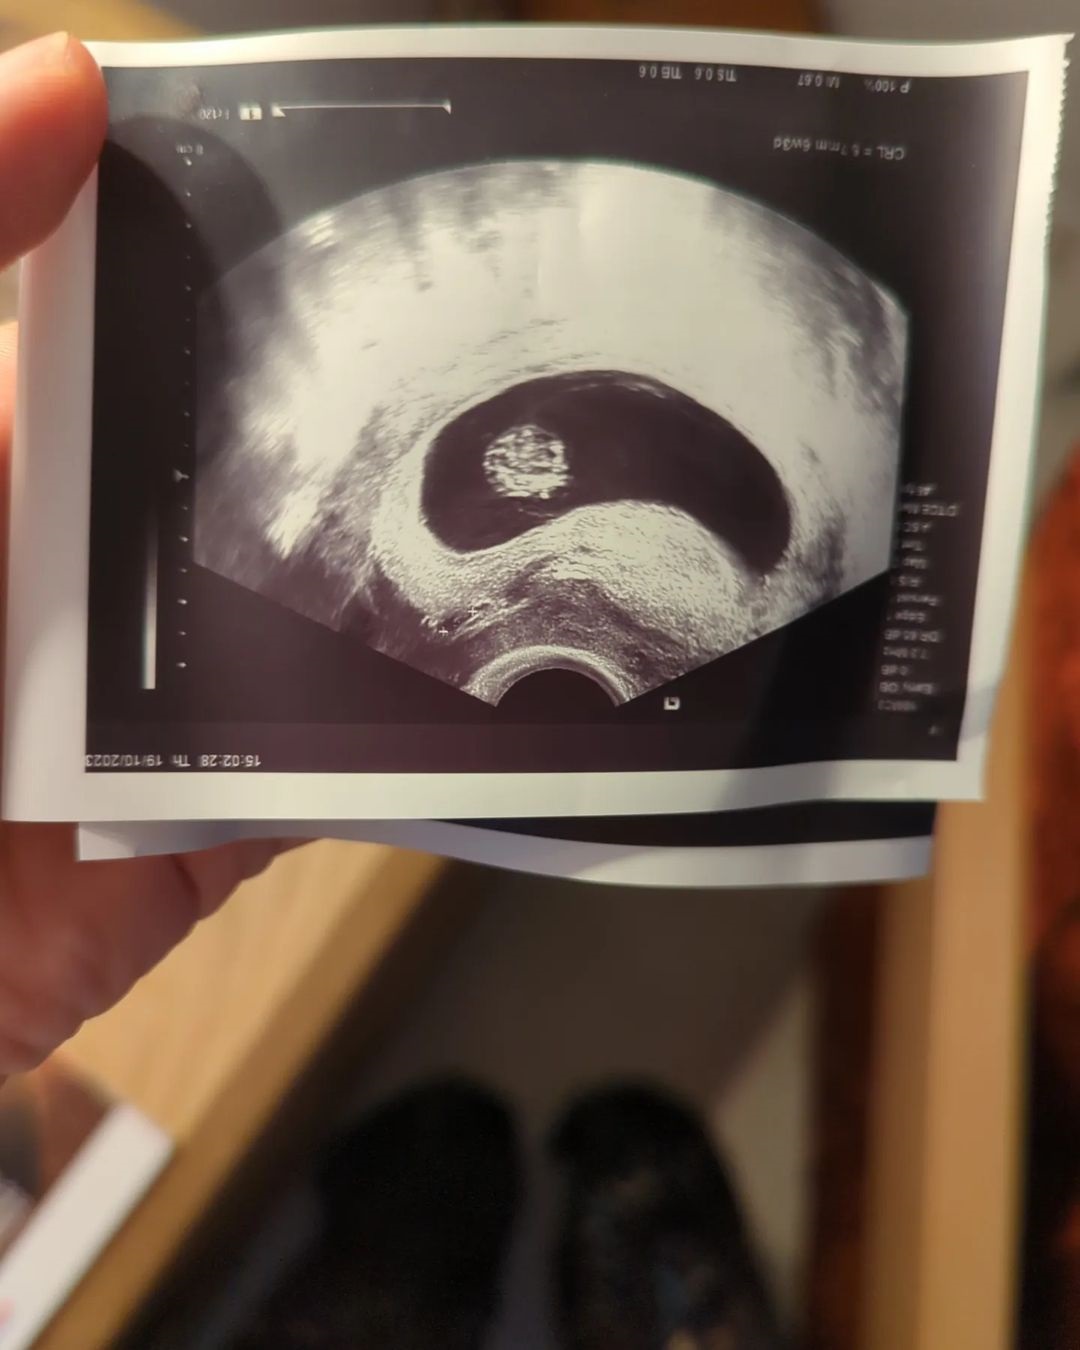

Συγκεκριμένα η Ντάνη Γιαννακοπούλου ανέβασε μια σειρά από σειρά από φωτογραφίες που δείχνουν την πορεία της εγκυμοσύνης της από την πρώτη μέρα που έμαθε το χαρμόσυνο γεγονός μέχρι και σήμερα.

«Δύο ψυχές, ένα σώμα» έγραψε η Ντάνη Γιαννακοπούλου στη λεζάντα της ανάρτησής της.